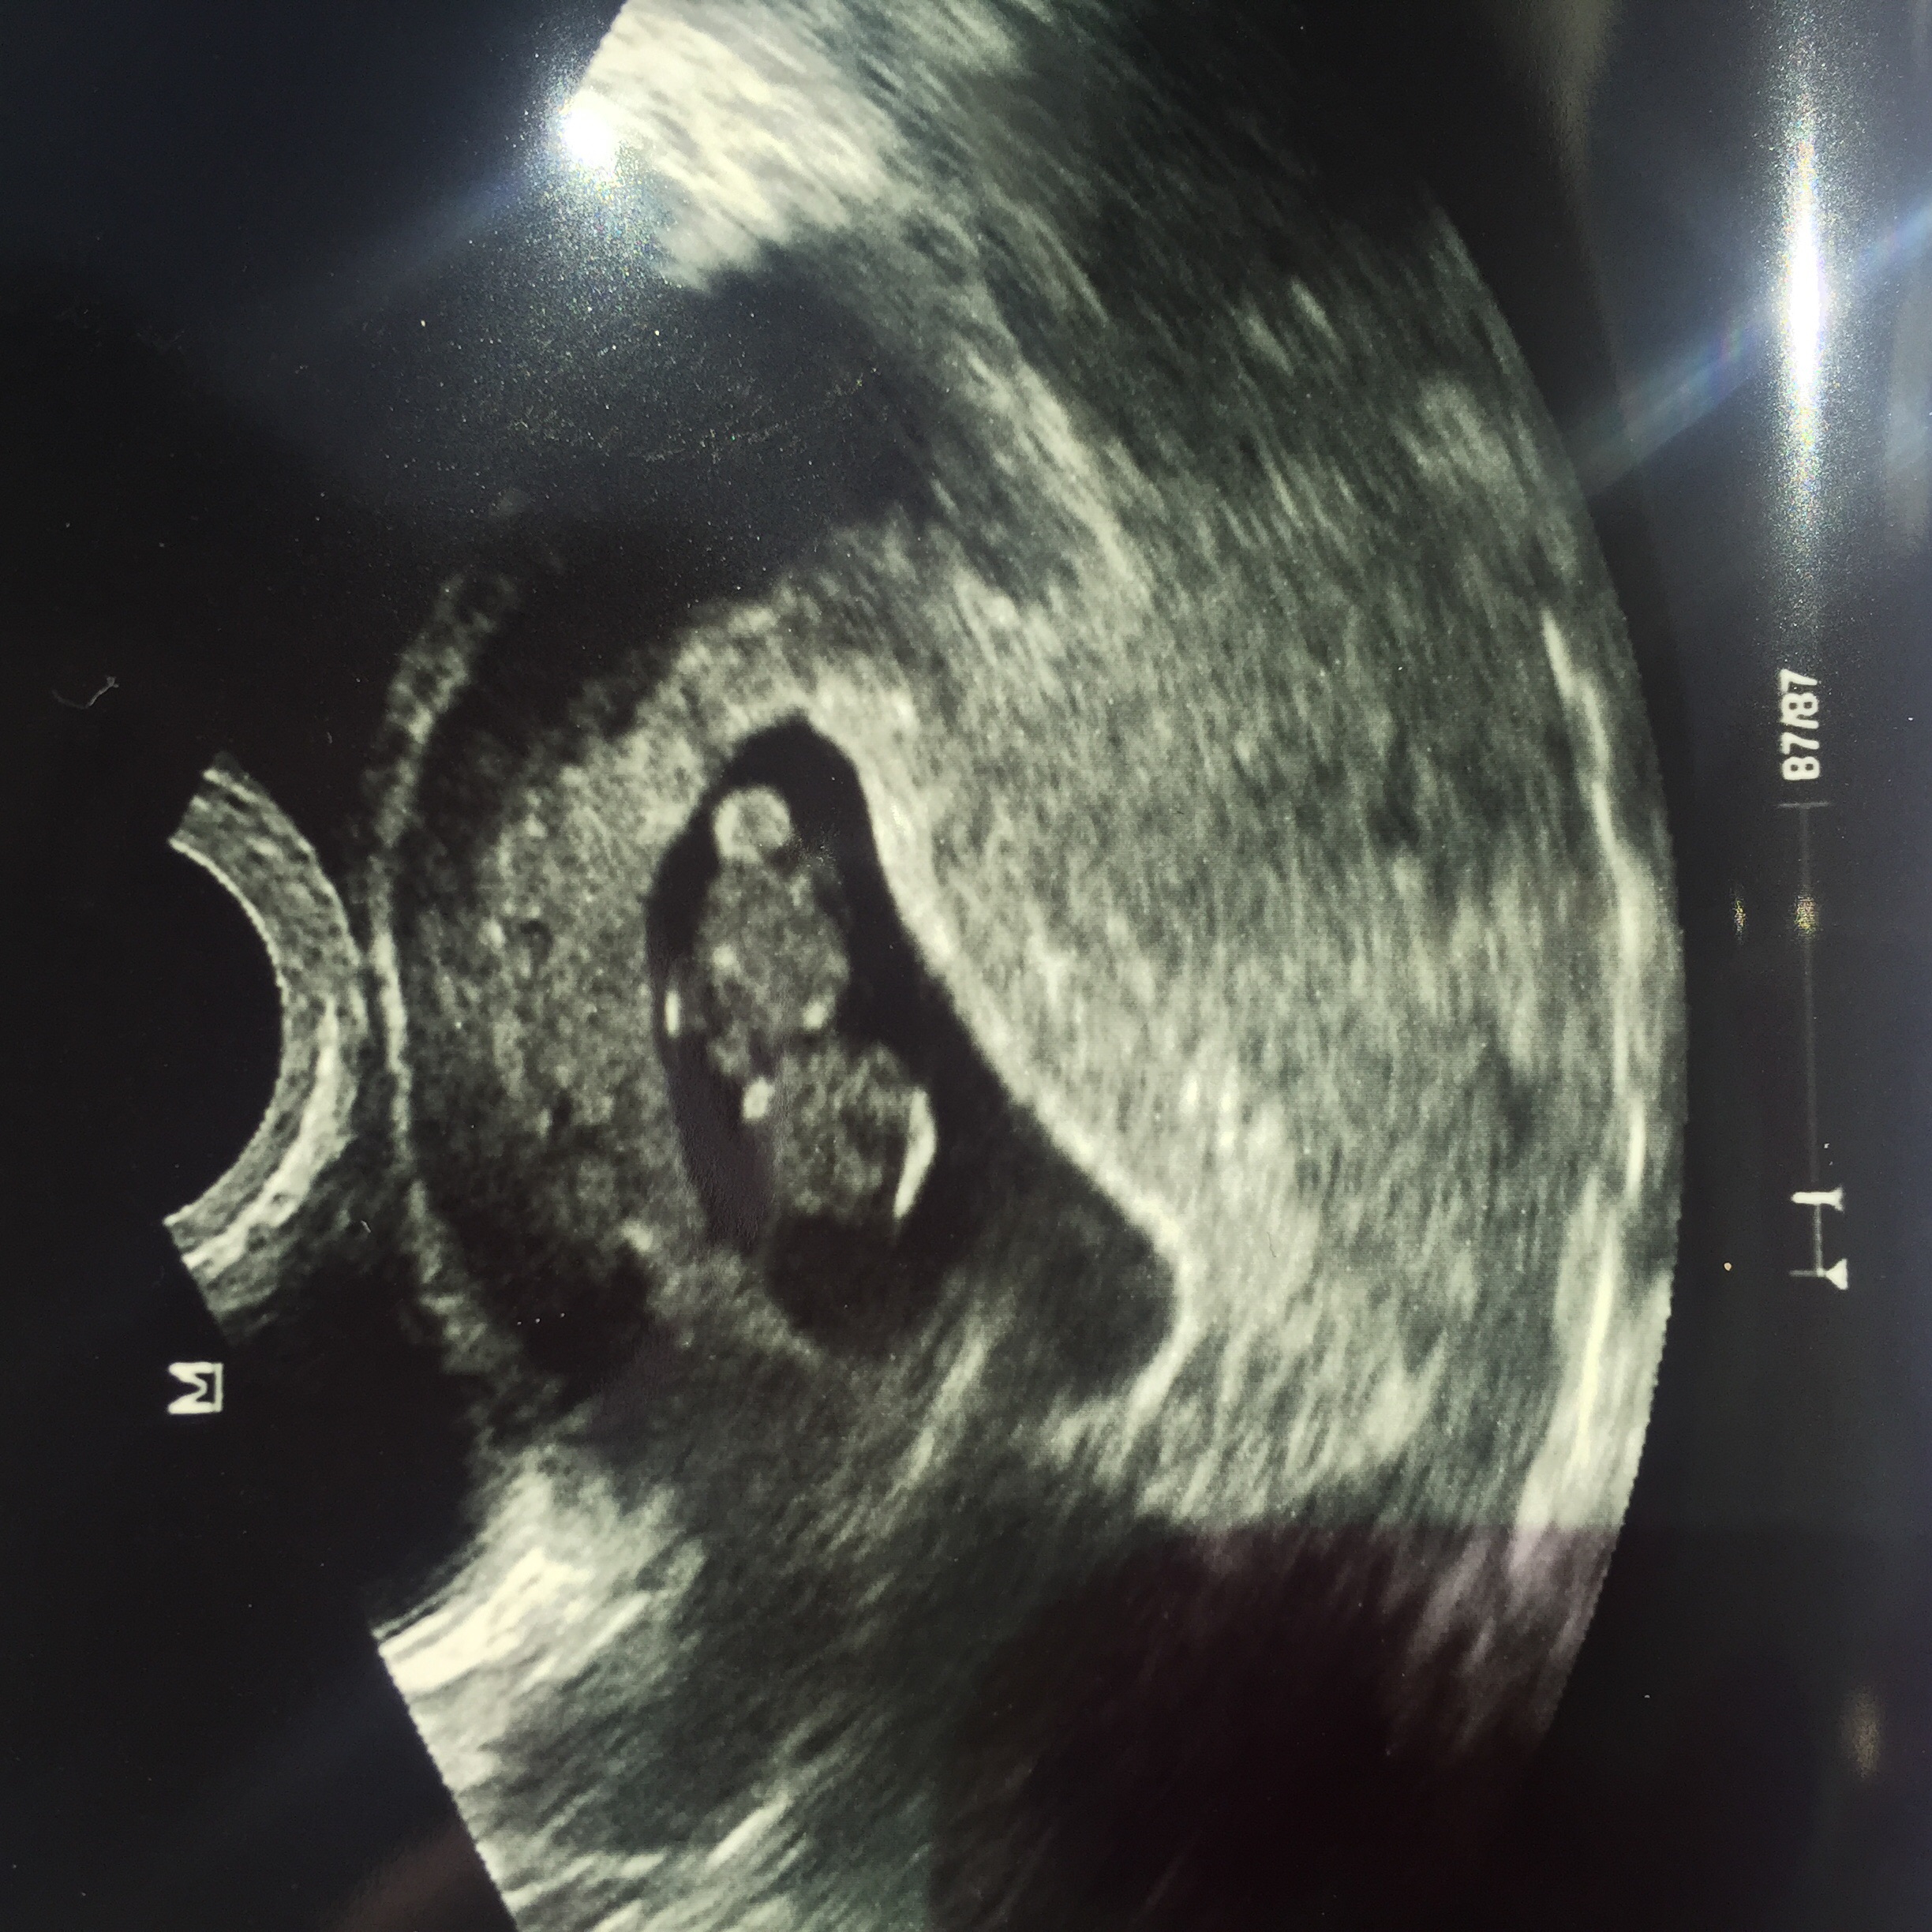

Measuring 2 days ahead of where we thought we were! Heart beat 120 bpm! What an amazing sound! Tears for this emotional momma!! I'm tearing up now even!

Slight bleeding in the top right of the photo that we are watching, but my doc says it's fairly common and should go away.

Due date May 15! Two days before my husband's birthday!